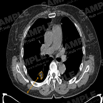

대표도면

대표도면 표

모달리티 폐암 영상데이터 데이터 포맷 어노테이션 항목 메타데이터 JSON 형식

CT 폐암 진단 의료 영상-대표도면-CT 예시 이미지 DICOM 단일 결절 부위

Polygon

체크

· DICOM 파일 (비식별화 후)

· age, sex, matrix size, machine name, slice thickness, series

description

· Json 파일 - 환자:json = 1:n

· Excel 파일 - 양성/악성정보 비식별 환자ID, 나이, 성별, 병리결과,

흡연력

(악성의 경우만 병리결과 수집)